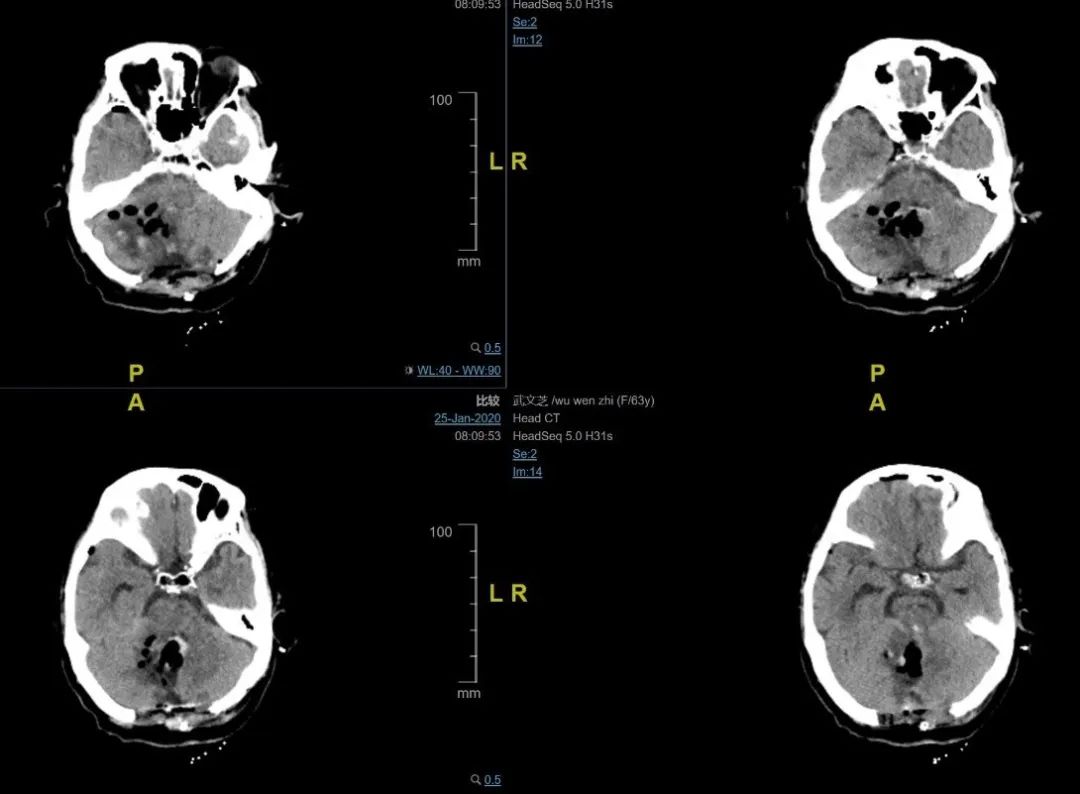

63岁患者求助于安全

2020年1月24日,除夕晚上8: 00,春节联欢晚会已经开始,值班的医务人员忙了一整天,此时只有吃饭的时间。一个突如其来的电话把值班的二线医生卢长宇叫到了急诊部。一小时前,一位63岁的女性病人正在家里吃团圆饭。和女儿说了几句话后,她突然头痛得厉害,立刻失去了知觉。当她的家人焦急地把她送到急诊室时,病人已经处于深度昏迷状态,GCS评分为5分。头部CT显示小脑出血,体积为20毫升。脑干受到压力。她的心脏停止了呼吸,心跳也随时停止。病人的女儿痛哭流涕,责怪自己伤害了母亲。

时间就是生命!神经外科主任赵元力接到报告后,果断指示“为中风和急诊手术开辟绿色通道”。这时,病人已经患有呼吸停止。卢长宇医生协助急诊医生迅速完成气管插管、术前检查和新冠状动脉肺炎筛查。仅仅40分钟,病人就被送到了手术室。赵元利主任、卢长宇和梁建锋医生的手术团队立即为患者实施了小脑血肿清除术和去骨瓣减压术。在显微镜下,赵元力主任迅速清除小脑血肿,解除脑干压迫,并小心保护脑干及重要神经和血管。手术结束时,病人的生命体征稳定,时间刚刚跳过零点。医院的医疗和麻醉团队在与死亡的斗争中实现了一个特殊的新年庆祝。

手术后第二天,病人睁开眼睛,拔出气管插管。她的女儿再也控制不住自己的眼泪,她母亲绕过了地狱之门,安全地回来了。

患者术前头部CT术前头部CT

患者术后6小时头部CT

头部CT术后6小时